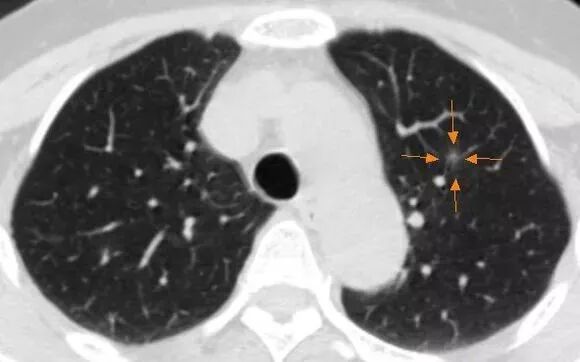

磨玻璃影(GGO)是一个非特异性医学词语,美国专业词汇命名委员会于1996年将其定义为肺实质内的局灶性密度增高影,其密度不足以掩盖其内的支气管及血管等结构,可见于气腔疾病、间质增厚、部分肺泡萎缩(肺不张)、毛细血管容量增加或以上的组合。

磨玻璃结节(GGN)定义为CT肺窗上呈现磨玻璃影表现的结节,其内支气管、血管等结构清晰可见,持续存在的肺磨玻璃结节为癌前病变或早期肺腺癌的可能性较大。

肺结节即影像学检查表现为直径≤3cm的局灶性、类圆形、密度增高的实性或亚实性肺部阴影,可为单个或多个,不伴肺不张、肺门淋巴结肿大和胸腔积液。根据大小可分为微小结节(直径<5mm)和小结节(5~10mm);根据成分可分为实性肺结节和亚实性肺结节,亚实性肺结节又可分为部分实性结节和纯磨玻璃样结节。以下主要通过CT表现区分良恶性结节。